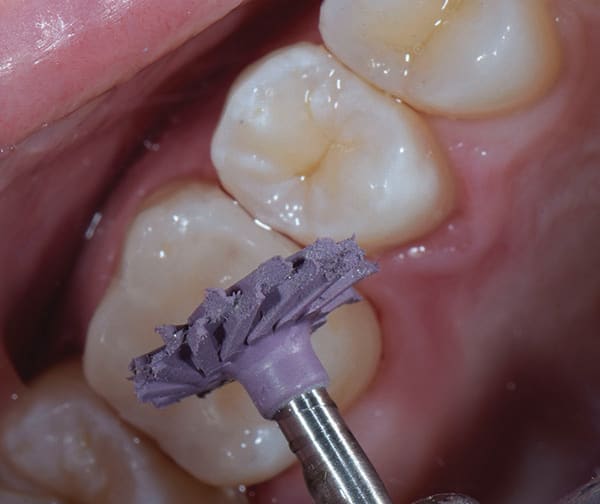

Once the operative field was isolated, a No. 557 carbide bur was used in a high-speed handpiece to efficiently remove the existing composite restoration and extend the preparation mesially. The Class II preparation was then refined using a fine diamond chamfer bur. Initial caries removal was performed using a round carbide bur in a slow-speed attachment (Figure 2). After initial caries removal, a caries indicating solution (Seek™ Caries Indicator, Ultradent) was used to stain any suspected remaining caries (Figure 3).4 Caries indicating solutions target demineralized dentin with a highly visible stain, providing an efficient and effective means of ensuring that only the infected dentin is subsequently removed, leaving the affected dentin behind (Figure 4).

Creating a high gloss finish was quickly achieved with a two-step diamond polishing system (A.S.A.P.® All Surface Access Polishers, Clinician's Choice). First, the purple pre-polishing spiral was used at 8,000 to10,000 RPM with a gentle sweeping motion for approximately 30 seconds (Figure 10). This was followed by the peach-colored final high shine polisher, which was used at the same speed and with the same motion but with a slightly lighter touch (Figure 11). The high luster result was almost instantaneous.